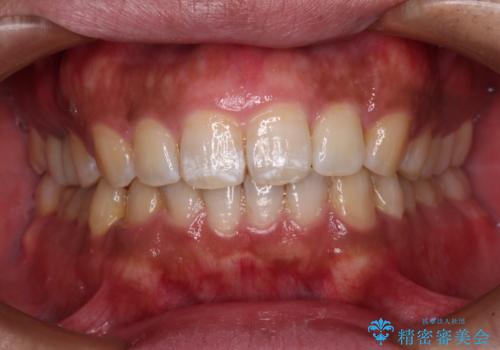

- 全体的な歯列の叢生を気にして来院された患者様です。

奥歯の咬み合わせを見ると、片方は上顎が下顎に対して相対的に前方にあり、他方は交叉した咬合の状態でした。

インビザライン単体で改善することも可能ですが、ディープバイトのためインビザライン単体で達成する可能性が低いと考えられたため、カリエール・ディスタライザーという補助装置を併用して、より確実性を上げることとしました。